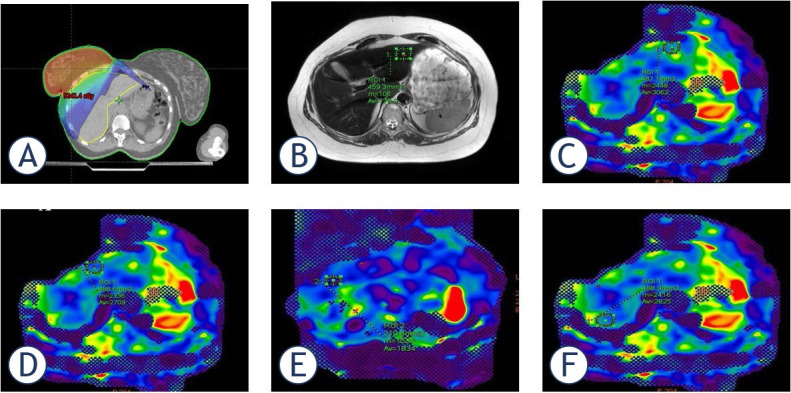

Background: In patients with right-sided breast cancer the liver can be partially irradiated during adjuvant radiotherapy (RT). We aimed to determine breast cancer RT effects on liver using with magnetic resonance elastography (MRE) and biological results.

Patients and methods: This retrospective study enrolled 34 patients diagnosed with right-sided breast cancer who underwent adjuvant RT. Liver segment assessments were conducted using MRE for all participants. Additionally, a complete blood count and liver enzyme analysis were performed for each patient. All measurements were taken both prior to the initiation and upon completion of RT.

Results: A statistically significant difference was found in ALT (p = 0.015), ALP (p = 0.026), total protein (p = 0.037), and albumin (p = 0.004) levels before and after RT. The highest mean liver stiffness (kPa) value was recorded in segment 8, while the lowest was observed in segment 6. A weak but statistically significant positive correlation was found between segment 5 stiffness and liver volume (p = 0.039). Additionally, a statistically significant positive correlation was detected between ALP levels and the stiffness values in segment 4A (p = 0.020) and segment 6 (p = 0.003). Conversely, a weak negative correlation was observed between the stiffness values in segment 8 and post-RT total protein levels (p = 0.031).

Conclusions: MRE can help us identify the level of fibrotic stiffness in the liver segments within the RT area without establishing clinical symptoms. MRE can support the clinician in evaluating the liver functions of right breast cancer patients who underwent RT. We assume these results will facilitate new studies with a large number of patients on MRE imaging at certain intervals in the follow-up of patients with right breast cancer who received RT before the development of radiation-induced liver disease (RILD).